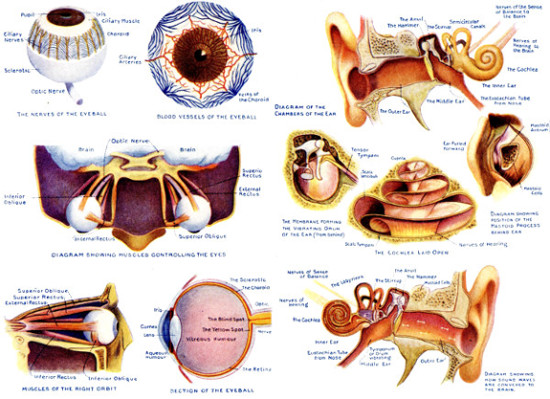

ITS STRUCTURE—ORGANIZATION INTO SYSTEMS—FUNCTIONS—SPECIAL SENSES—NERVOUS SYSTEM—PERSONAL HYGIENE—PREVENTION OF DISEASE—INTERDEPENDENCE OF BODY AND MIND—EUGENICS—ILLUSTRATIONS AND CHARTS.

Picture Diagrams of Eye and Ear